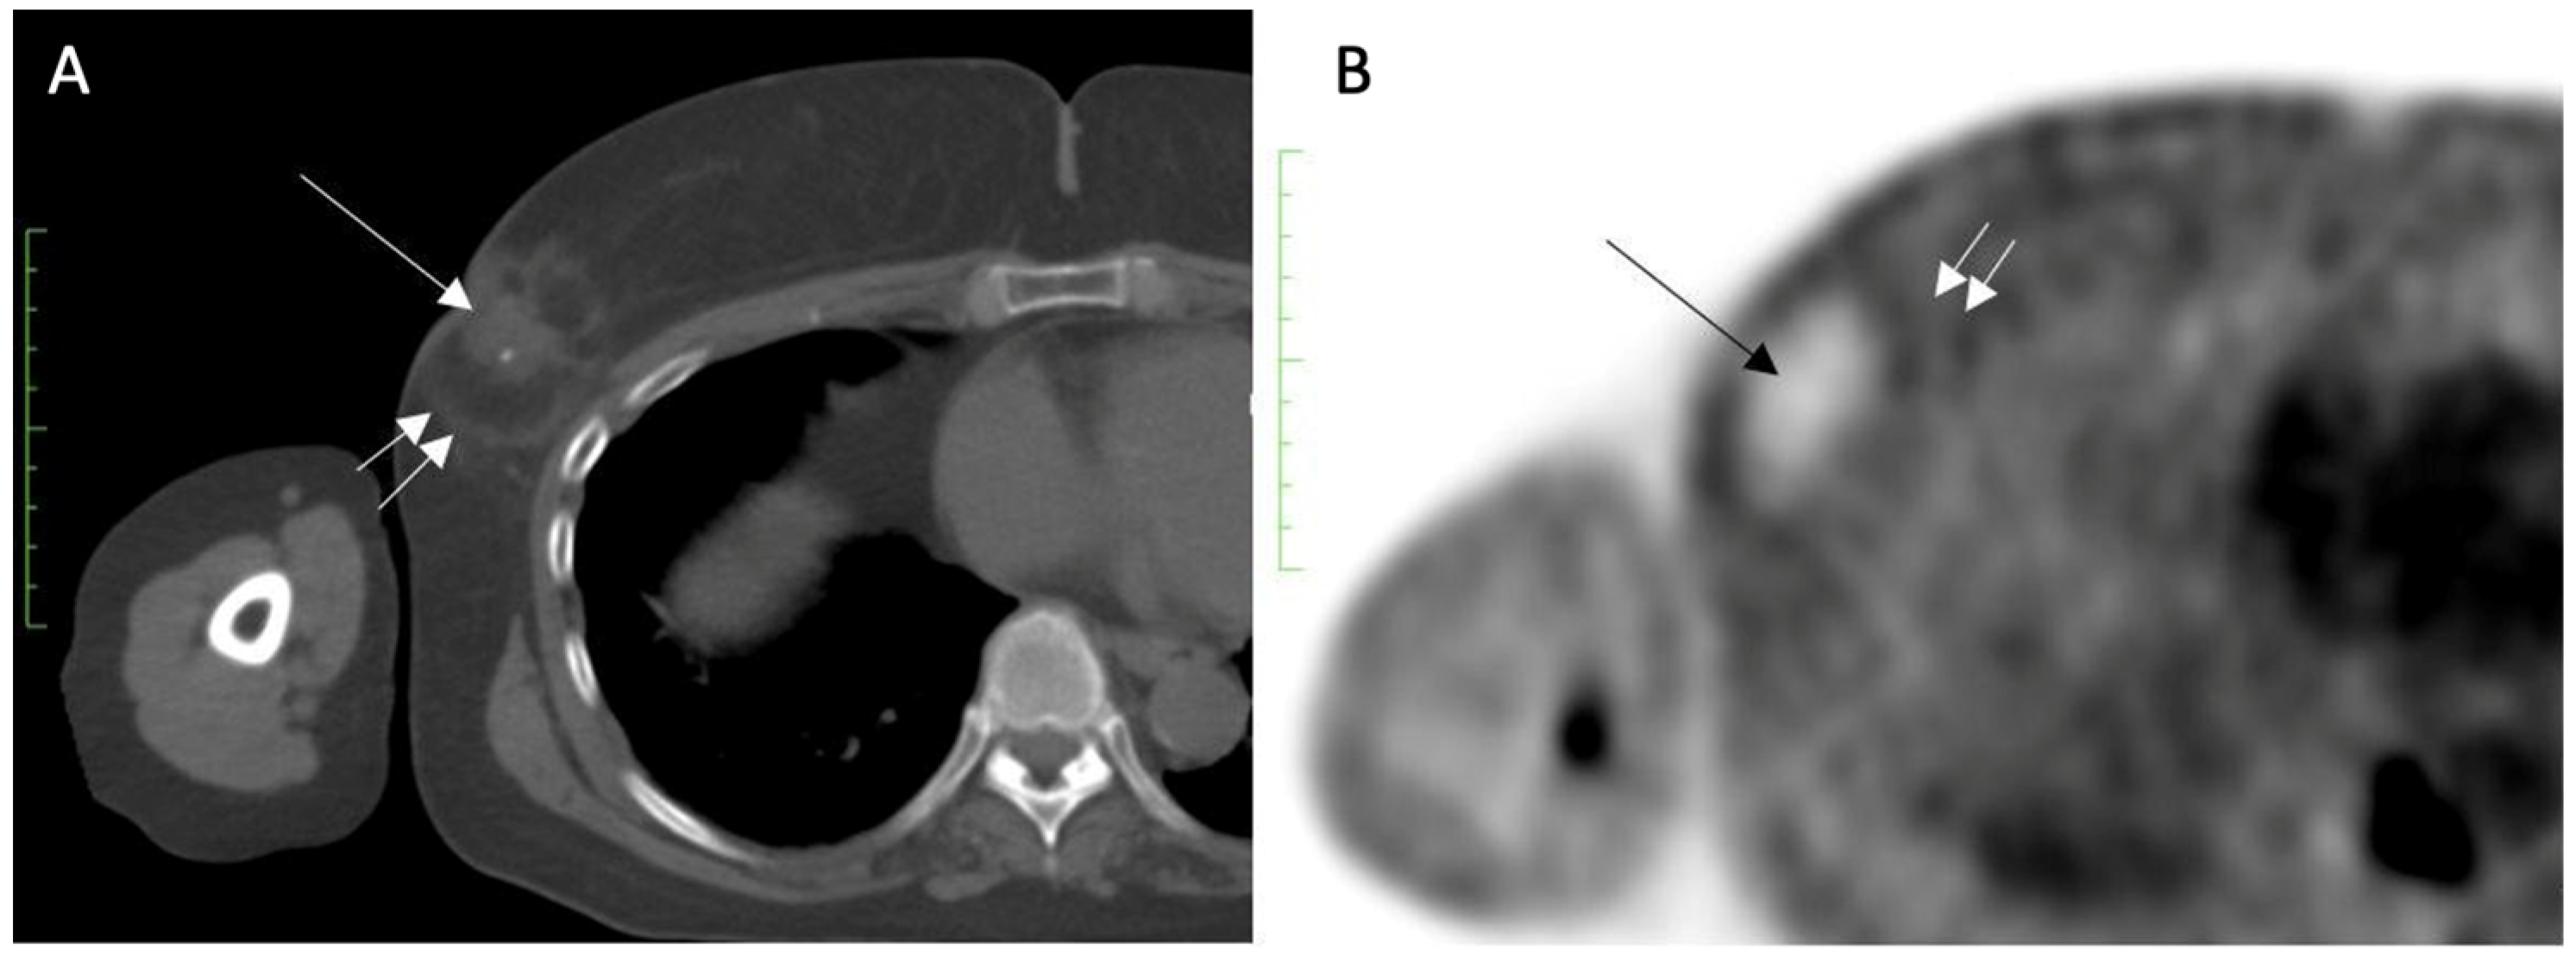

Contrast-Enhanced Breast MRI. Contrast enhanced breast MRI improves assessment of disease extent, including detection of spiculations, multifocal, multicentric, or contralateral disease, which might impact eligibility for cryoablation or alter the overall treatment plan (Figure 4). Contrast-enhanced breast MRI has the added value of permitting 3-D image reconstruction to permit viewing of the tumor from various angles for a more comprehensive assessment of tumor shape and size. Breast MRI for cancer evaluation requires the use of an intravenous contrast containing gadolinium that can be safely administered with minimal short-term and long-term risks. However, patients unwilling or unable to receive gadolinium might be able to access dedicated breast-only diffusion weighted MRI, which has limited availability in the U.S.

Figure 4.

Contrast-enhanced breast MRI image showing multifocal disease indicated by mass-like enhancement of dominant mass (indicated by single arrow and encircled with hash marks) as well as mass-like enhancement of a second focus of disease (indicated by double arrows and encircled with hash marks). The second focus was mammographically-occult.